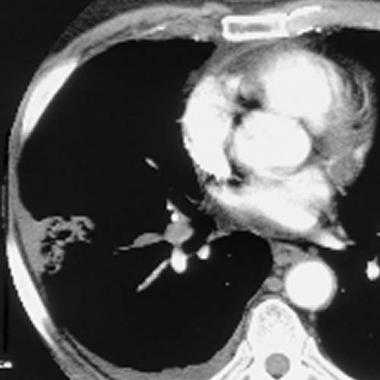

Спиральная КТ с контрастным усилением позволяет законтрастировать просвет легочных сосудов и увидеть тромб в их просвете. У молодого мужчины после межконтинентального перелета возникла острая боль в груди и нарушение дыхания. КТ визуализирует тромб в артерии переднего сегмента верхней доли левого легкого ( LA 2) и артерии переднего сегмента верхней доли правого легкого ( RA 2).